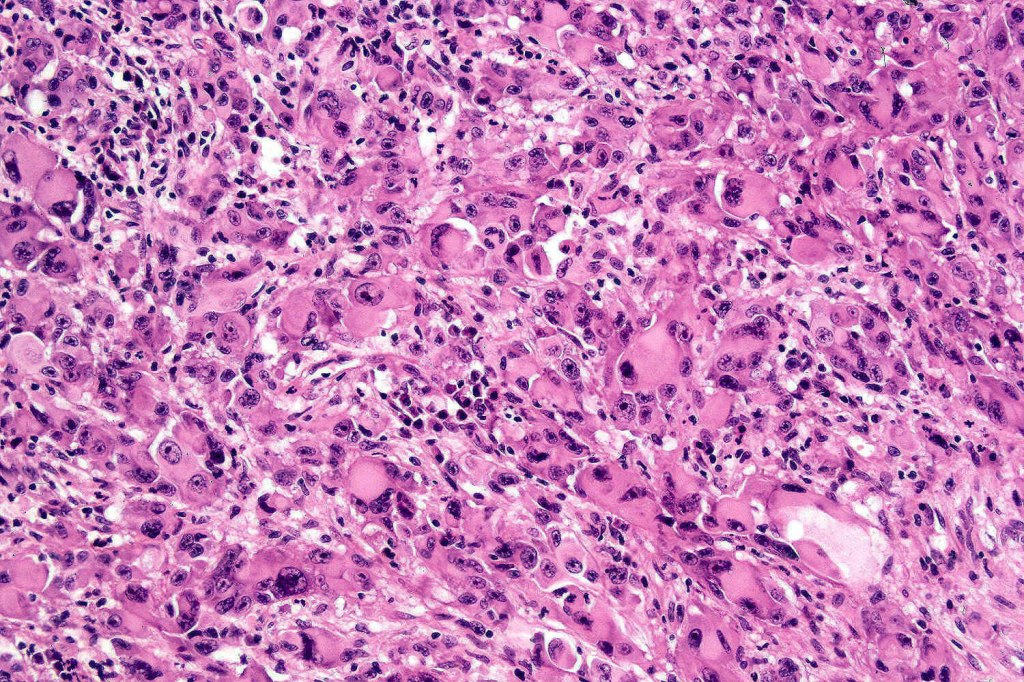

•Extremely rare often amelanotic, high-grade variant (based on the majority of documented cases representing metastases. The biological potential of primary tumors with rhabdoid features is uncertain owing to the paucity of reported cases)

•Metastases & recurrent disease>>primary tumors

•Characterized by pleomorphic tumor cells with large eosinophilic, hyaline globular inclusions and eccentric vesicular nuclei containing prominent nucleoli, mitoses often conspicuous

•Very sparse melanin pigment may be identified